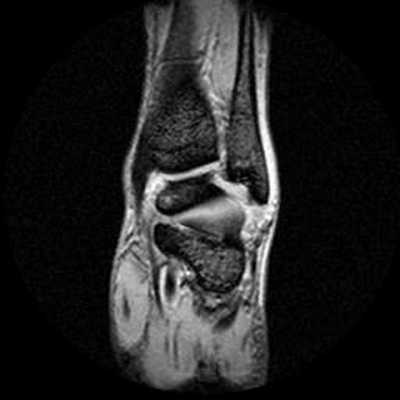

МРТ голеностопного сустава является приоритетным методом диагностики повреждений сухожилий, связок и мышц . Поэтому при переломе лодыжки, сопряженном с суставными травмами, следует сделать магнитно-резонансную томографию.

Что покажет магнитно-резонансная томографияпри переломе лодыжки

МРТ голеностопа использует сильное магнитное поле для создания очень подробных изображений связок, которые помогают удерживать лодыжку вместе.

Что показывает МРТ голеностопного сустава

Поэтому МРТ широко используют в ортопедии и травматологии, онкологии. Вот, что показывает МРТ голеностопа:

Травматические повреждения голеностопа, щиколотки, пальцев стопы.

Состояние после травм голеностопа, чтобы выявить наличие и характер поражения связок (растяжение, разрыв), мышц (ушибы, размозжение, некроз), сухожилий, сосудов (кровоизлияния в мягкие ткани), костей, суставов (вывихи, подвывихи, внутрисуставные переломы). Перелом обычно хорошо виден на рентгенограмме, но сопутствующие повреждения окружающих тканей видны только на МРТ.

При дегенеративно-дистрофических процессах человек жалуется на боль в стопе, лодыжках, хруст в суставе, заклинивание, ограничение движений. Боль максимально выражена в начале движения, затем постепенно проходит по мере того, как человек «расходится». На МР снимках видно, насколько разрушен хрящ, есть ли изменения костной ткани под хрящевым слоем. Сначала хрящ истончается, сужается щель между суставными концами костей. Затем видны небольшие очаги разрушения хрящевой пластины, которые постепенно увеличиваются. Компенсаторно увеличивается плотность костной ткани на границе с хрящом. Могут выявляться очаги рассасывания в кости, экзостозы - костные наросты, которые травмируют соседние ткани.